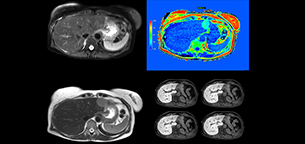

Dr. Kukuk’s liver exam begins with T2-weighted imaging, single shot and with fat suppression. “We always perform diffusion weighted imaging (DWI) with four b-values (0, 50, 250, 800) for lesion characterization, for monitoring after therapies, and for visualization of small lesions. Before giving contrast we routinely use the mDIXON Quant fat quantification sequence. Then we use dynamic e-THRIVE with an in-plane spatial resolution of 1.5 mm and high temporal resolution in just four breathholds of 13.1 seconds.” “Contrast enhancement is important to help us characterize lesions, for follow up in oncology patients and to inform clinicians when deciding on possible changes in the therapeutic regimen,” Dr. Kukuk explains. “Because we use liver-specific contrast agents we can obtain the T2-weighted images after the dynamic, to bridge the waiting time needed with these contrast agents. Just before the patient leaves the scanner we acquire another e-THRIVE in the axial plane and one or two coronals.”

“We have performed a study comparing mDIXON Quant fat percentages with results from histopathology. The correlation with different histologic methods was very good and also the correlation with MR spectroscopy was far above 0.9 – a nearly perfect correlation,” says Dr. Kukuk.

“So, this fast mDIXON Quant sequence allows us to diagnose, quantify, and follow up – that’s the real advantage. Our gastroenterologists were easily convinced, as they are well aware of the limitations of ultrasound and the risks of liver biopsy.”

“Fatty liver disease is a common condition. Studies found a prevalence of non-alcoholic fatty liver disease in up to 44% in the general European population [1]. Liver fat cannot be quantified by ultrasound or CT, so biopsy has been the way to quantify fatty liver disease so far,” says Dr. Kukuk. “mDIXON Quant now allows non-invasive quantification of liver fat, which is valuable for both diagnosis and follow-up during dietary changes or therapy, for instance in hepatitis C.”

“The mDIXON Quant fat fraction maps provide quantitative information and also anatomical detail. The sequence is fast, usually taking about 16 seconds, which is just a breath hold for most patients. It definitely improves our efficiency.”